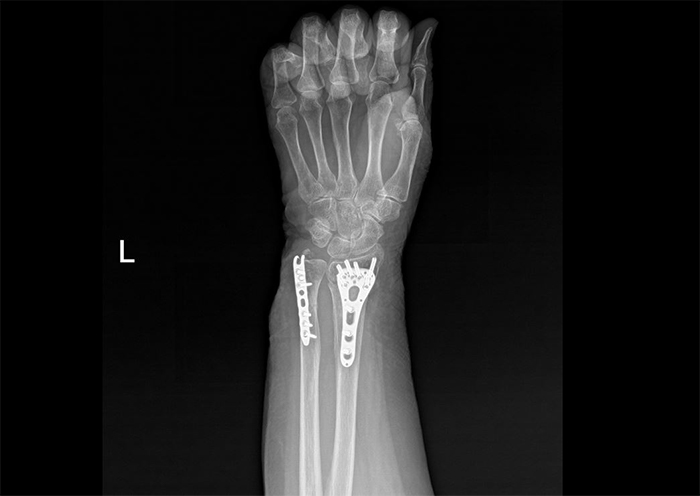

진단명:

Fx. distal radius and ulna wrist Lt.

좌측 요척골 원위부 골절

진단명은 좌측 요척골 원위부(손목 부위) 골절이었는데요. 영상 사진을 보시면 손목 뼈 부위에 금이 가 있는 것을 확인하실 수 있습니다. 손목 뼈는 수시로 움직이는 중요한 관절에 연결되어 있습니다. 그래서 조금만 잘못 붙더라도 지속적인 통증이나 관절염 증상이 나타날 수 있습니다.

그러므로 세밀하고 안정적인 골유합이 필수적인데요. 관혈적 정복술을 시행하여 금속판과 못을 삽입하여 골절된 뼈를 단단하게 고정하는 수술을 시행하였습니다.